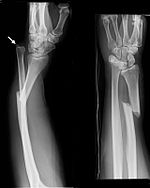

Galeazzi fracture Ricardo Galeazzi radius shaft fracture with dislocation of distal radioulnar joint blow to forearm Galeazzi fracture Archived 2017-12-01 at the Wayback Machine at eMedicine Galeazzifraktur 1 THWZ.jpg

Monteggia fracture Giovanni Battista Monteggia proximal ulna fracture with dislocation of radial head blow to forearm Monteggia fracture at Who Named It? Monteggia Fracture.jpg